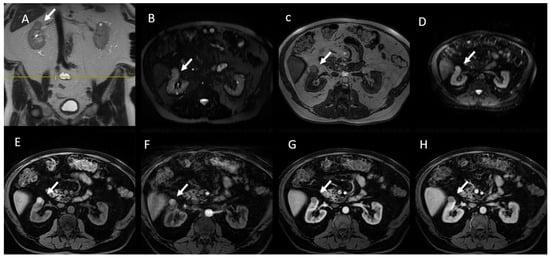

- (d) Class III: indeterminate cystic mass, which includes cystic masses characterized by one or more thickened (≥4 mm) or enhancing and irregular (≤3 mm and with convex marginal protrusions) walls or septa [91]. Bosniak III masses (Figure 4) are “potentially” malignant in that they have an intermediate probability of malignancy (about 55%) [97]. Therefore, urologic consultation should be considered for possible partial nephrectomy or radiofrequency ablation in candidates unfit for surgery [99].